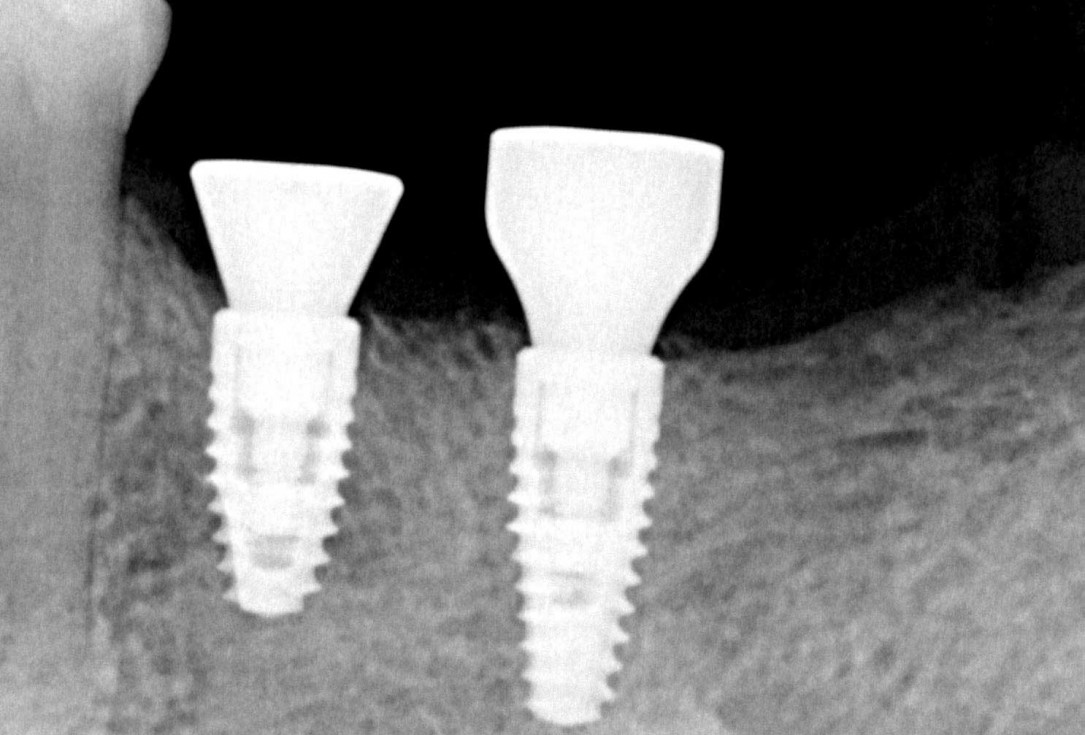

Three implants placed in a narrow posterior mandible